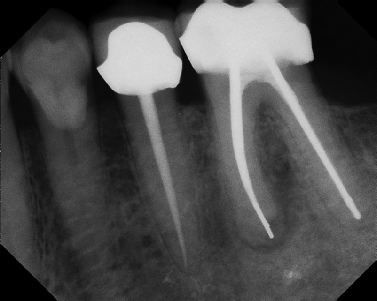

Root Canal Retreatment - Meriden 8 mos. recall Post-op Pre-op